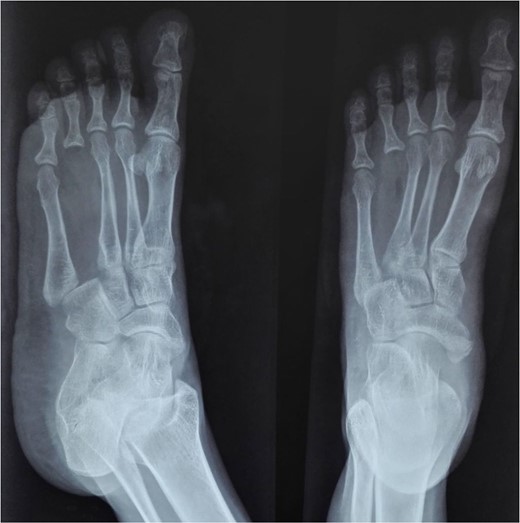

At 2 years postoperatively, the patient showed excellent functional outcomes. Radiographs demonstrated a stable MCP joint with well-preserved joint space, indicating successful graft incorporation (Fig. 3). Donor site radiographs at 2 years showed appropriate spacing between the third and fifth metatarsals with no evidence of arch collapse or stress reaction in the adjacent bones (Fig. 4). The patient achieved an active MCP joint range of motion of 0–80 deg (Fig. 5).

Post-operative radiograph showing preserved joint space and structure of transferred metatarsal.